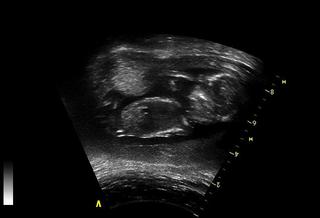

@monn tady mrně hezky mává... Ale několikrát během ultrazvuku se k nám otočilo zády... ať prý nevejráme 😀

@majcam hele když koukám na tu vytištěnou velkou fotku, tak tam taky něco mezi nožičkama vidím... ale vzhledem k tomu, že to má mimi až skoro ke kolenům, tak to tipuju spíš na pupeční šňůru. Ale manžel jak to viděl, tak si taky hned dělal prdelky, že to asi bude chlapák po tatínkovi 😀 😀

@petaloudi: krasna fotka.... 😀